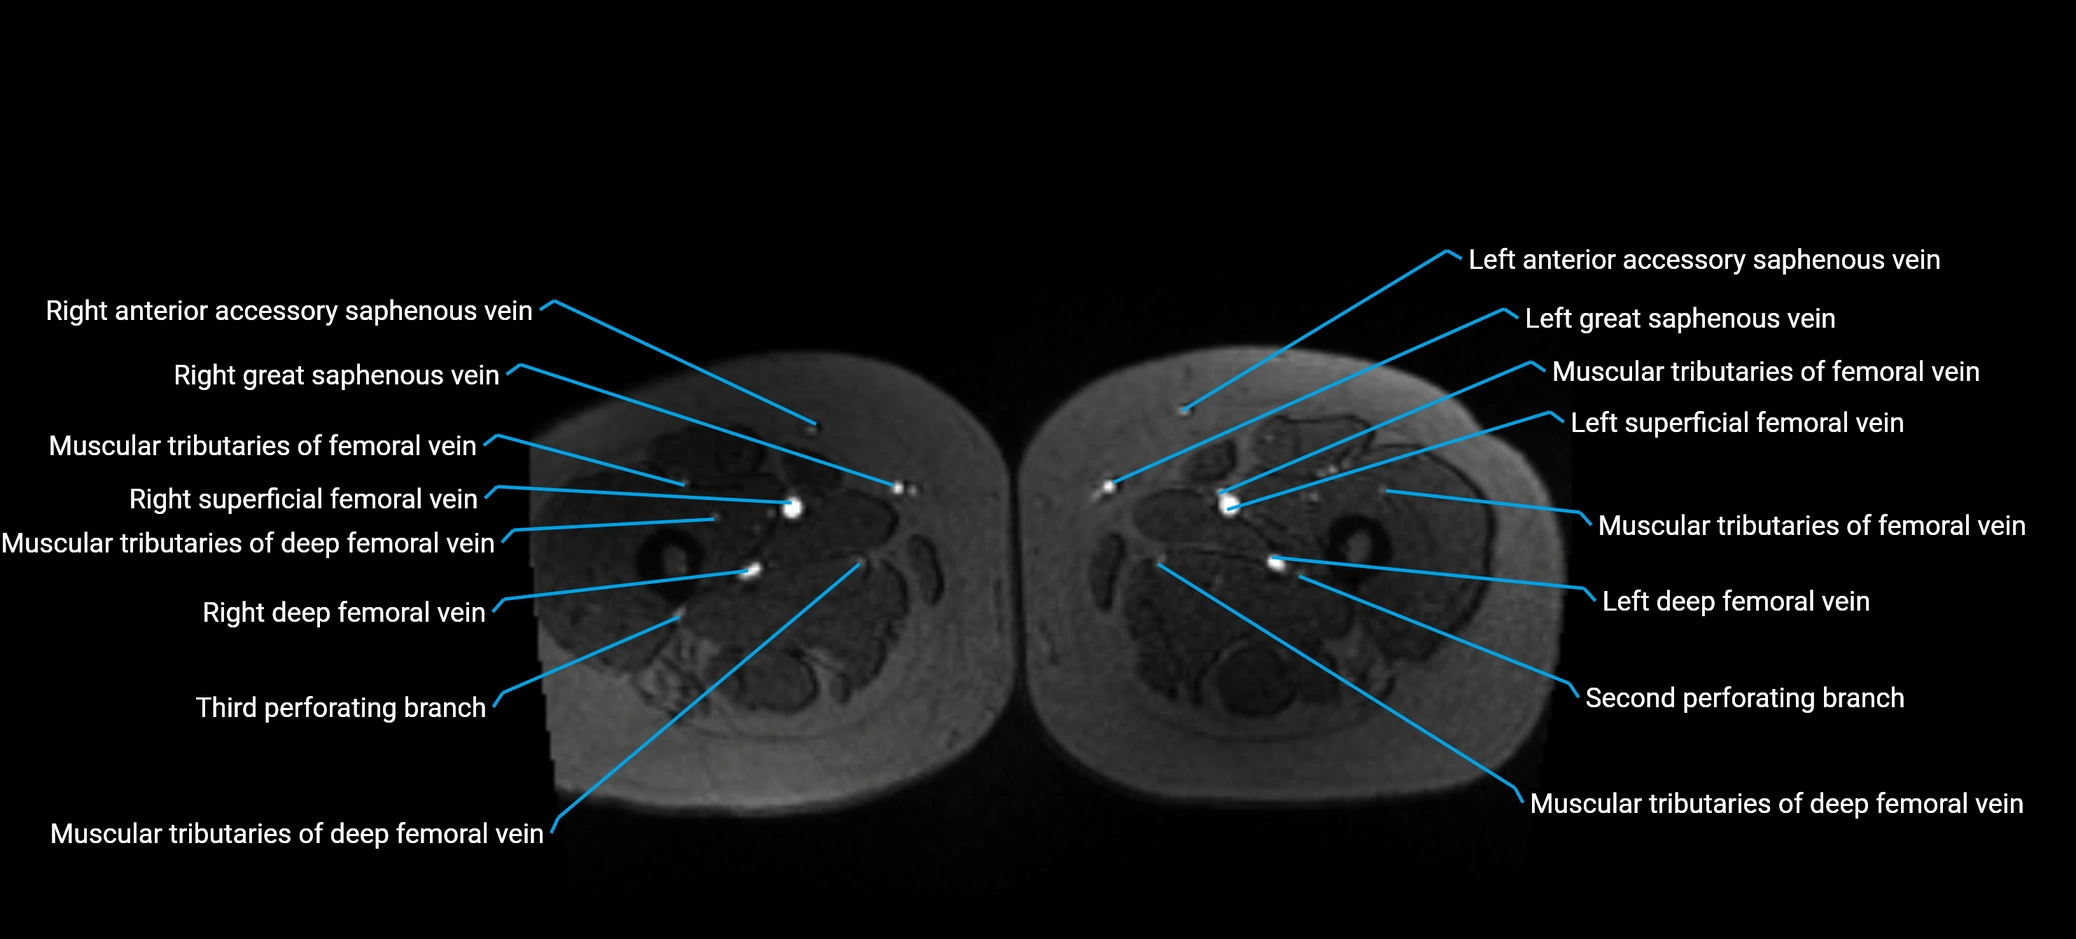

MRV TOF (Time-of-Flight MR Venography):

• Appears as a bright, high-signal vascular channel representing flowing blood

• Clearly shows branching pattern of right portal vein into anterior and posterior branches

• Best in coronal or axial reconstructions for segmental mapping

• No need for contrast, relies on flow-related enhancement